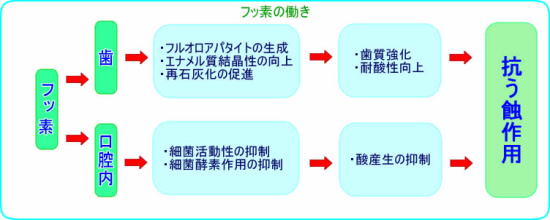

フッ化物の予防メカニズム

フッ化物には歯に対する作用として「フルオロアパタイトの生成」、「結晶性の向上」、「再石灰化の促進」また、口腔内の環境に対しての作用として「細菌活動性の抑制」、「細菌酵素作用の抑制」の二つに大きく分けられます。

フッ化物が歯のエナメル質に作用しますと、エナメル質の主成分であるハイドロキシアパタイトと置換してフルオロアパタイトを生成します。これにより、エナメル質はより安定したより強い結晶構造を持つようになり、耐酸性を向上することになります。

また、唾液中に存在するCaイオン、リン酸イオンとともに歯に再沈着し壊れた結晶構造を修復します。これを再石灰化と呼んでいます。

またフッ化物には、細菌が糖分を菌体内に取り込んでエネルギーを作る過程で必要なエラノーゼという酵素の活性を阻害する働きを持っています。つまり、口腔内にフッ化物が存在することによって、細菌はエネルギーを産生できなくなり、結果として酸を作ることができない環境を作り出します。